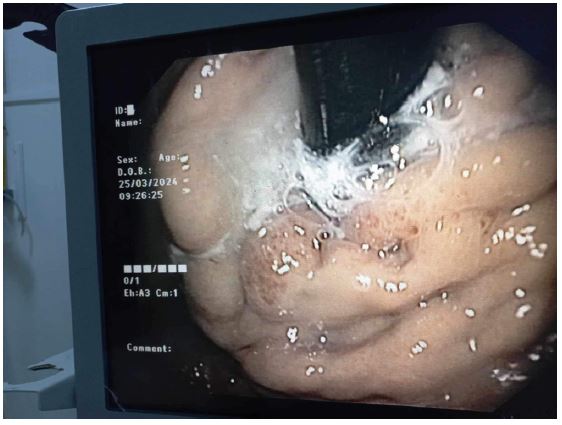

Following the procedure, there was a drop in oxygen saturation and development of tachycardia. The patient was subsequently intubated, ventilated, and transferred to a monitored setting. Thoracic CT angiography revealed bilateral massive non-thrombotic pulmonary embolism with dense infiltrates in pulmonary arterial areas affecting all segmental arterial branches. Embolization material was noted in the splenic vein (Figure 2). Intravenous steroids (dexamethasone 6 mg/day for 2 days, then gradually decrease by 2 mg every 2 days) and supportive management were initiated. Over the next two days, the patient’s oxygen requirements gradually decreased. She was successfully weaned off ventilation, extubated, and discharged home.

Figure 2: Coronal CT scan of the abdomen reveals high-density material in the upper left abdomen, indicating the presence of iodized glue and microcoil embolization of the gastric varix (solid arrows) and splenic vein (arrow). Thoracic images show multiple high-density filling defects in the pulmonary arteries, consistent with non-thrombotic embolization of iodized glue (arrowheads).